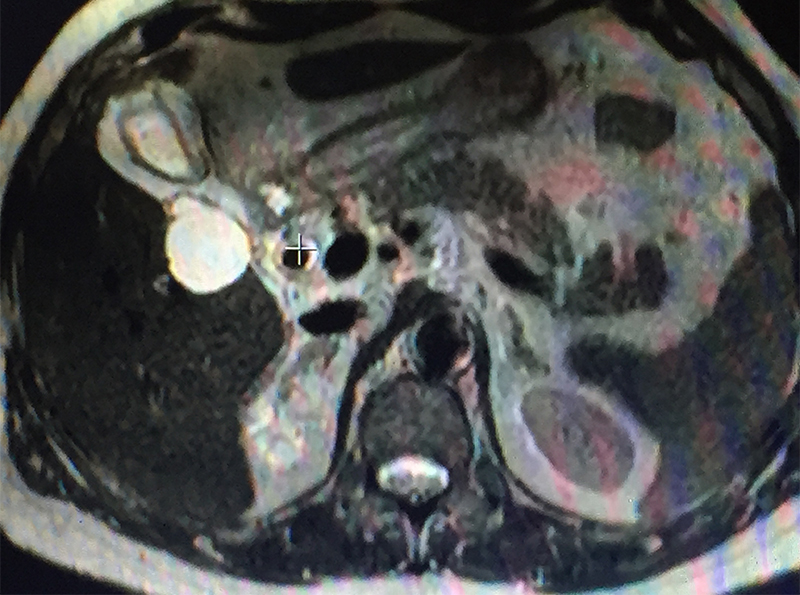

79 year old gentleman with diabetes, hypertension, cardiac problems, previous coronary bypass surgery and borderline renal function presented with acute abdominal pain in the right upper abdomen & periumbilical area, vomiting, abdominal bloating / distension and not passing gases. He had one episode of high grade fever too. Initial investigations (blood & abdominal sonography) showed evidence of infection (high leucocyte count & CRP), jaundice (raised bilirubin), biliary infection / inflammation – cholecystitis / cholangitis -- (raised SGOT / SGPT / alkaline phosphatase -- liver enzymes), mild pancreatitis (raised amylase / lipase –pancreatic enzymes) and worsening renal function (BUN / creatinine). The ultrasonography showed stones in the gall bladder with severe cholecystitis (gall bladder inflammation / swelling), large stones in the bile duct and pancreatitis (inflammation / swelling of pancreas). The patient was diagnosed with acute calculous cholecystitis, obstructive jaundice & cholangitis due to stones in the bile duct, acute biliary pancreatitis (pancreatitis caused by passage of stone / obstruction of mouth of the common channel of bile & pancreatic duct). The vomiting, dehydration & infection had caused acute injury to the already compromised kidney (due to diabetes & hypertension) leading to further worsening of the renal function. A MRCP (MRI examination of biliary / pancreatic ducts) & IV contrast MRI abdomen was done to confirm the diagnosis. The pancreatitis was fortunately mild on MRI.